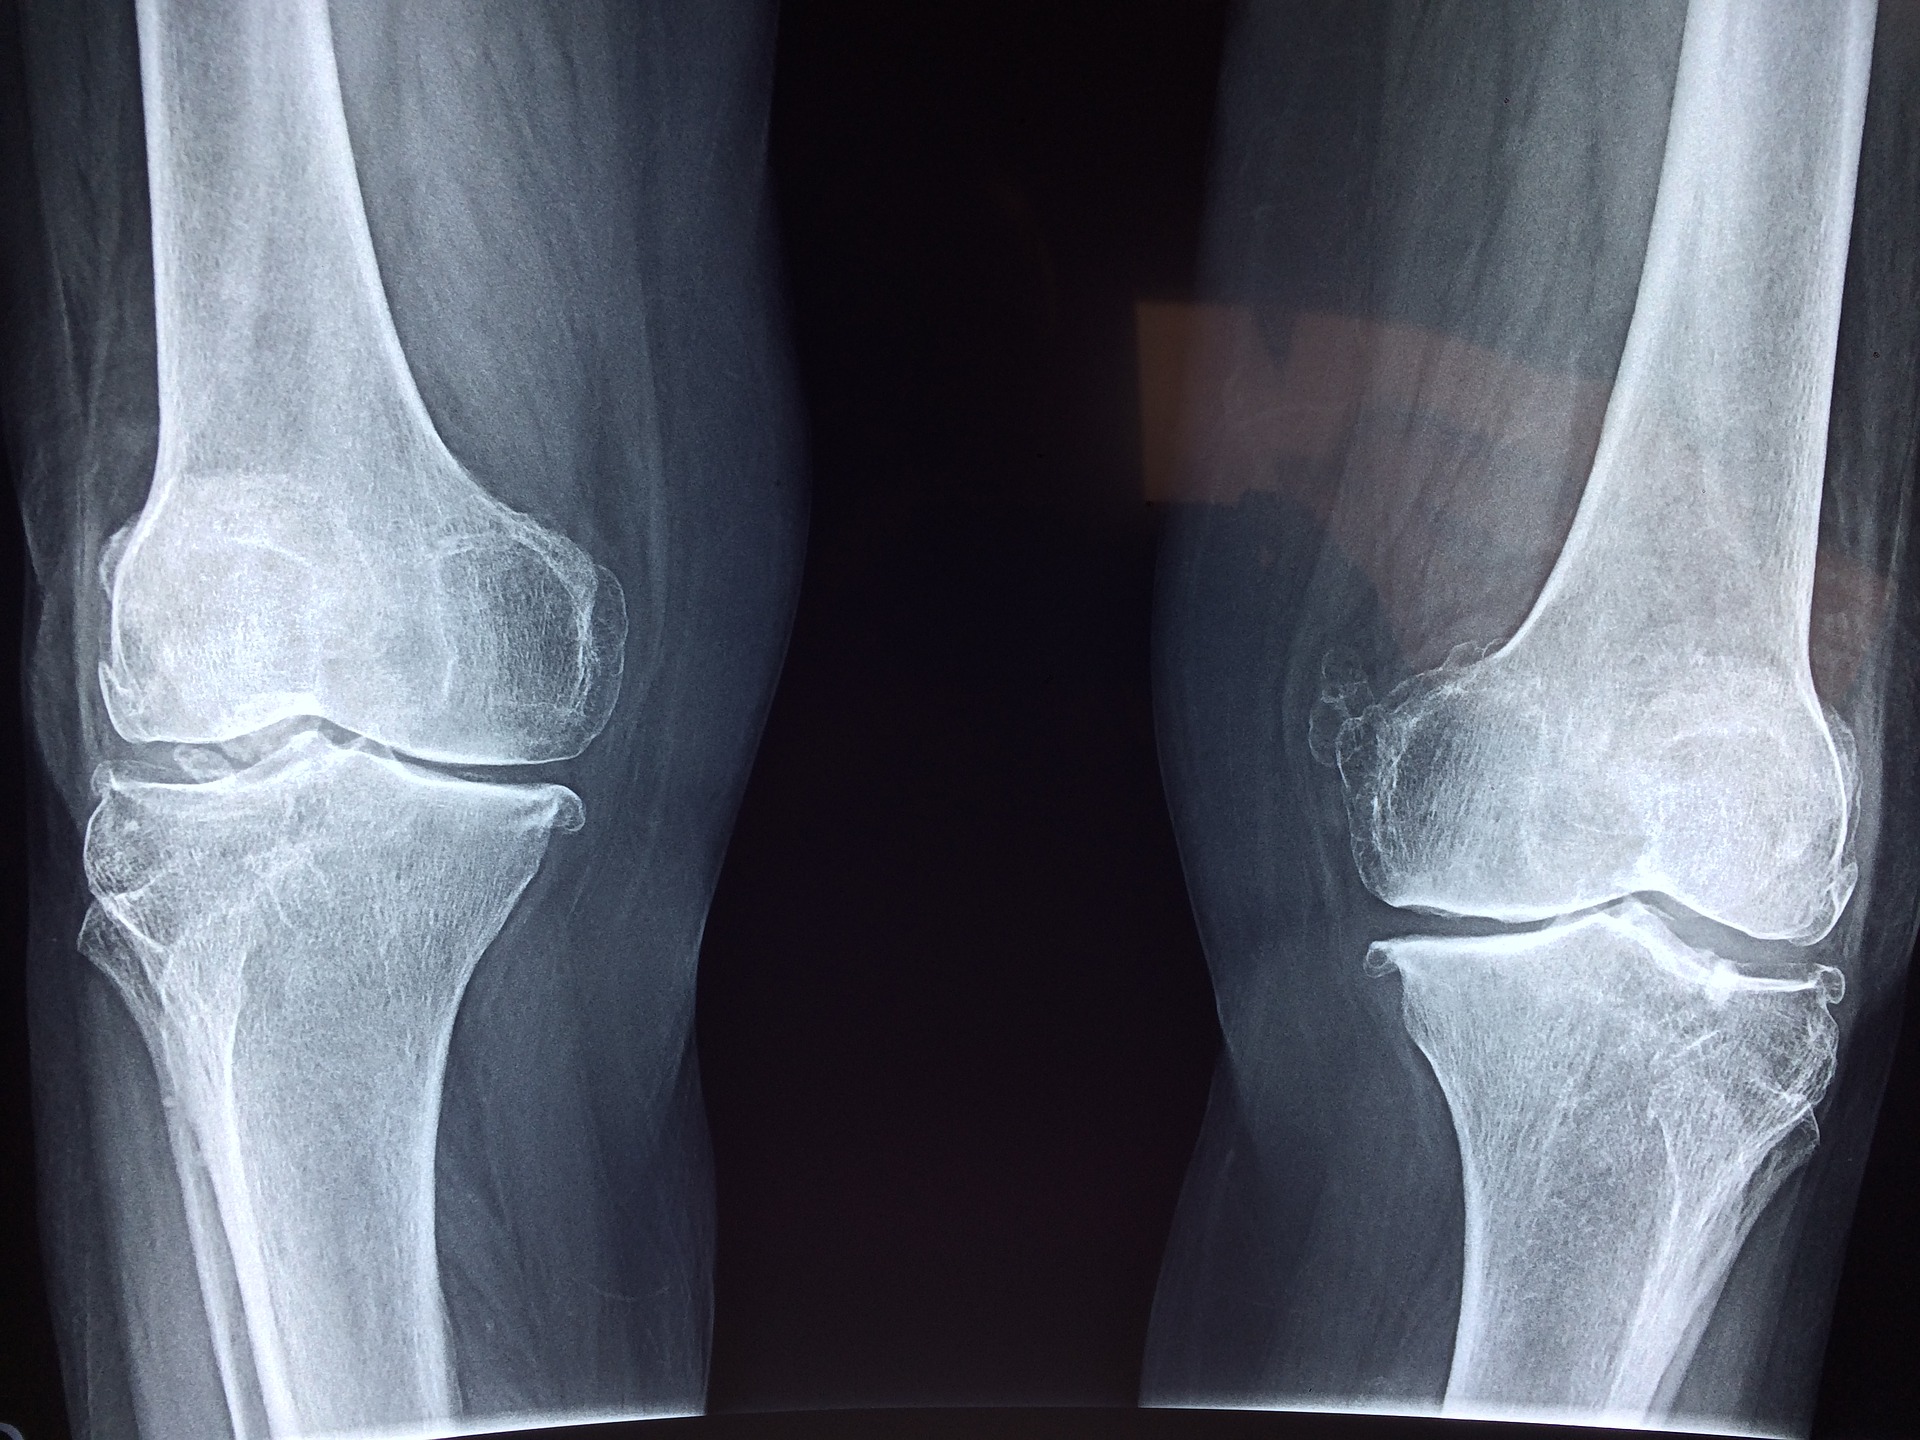

Sabemos o quanto ter Artrose no joelho pode ser limitante.

Dor ao caminhar, agachar, subir escadas, dificuldade pra dobrar o joelho, dor ao dormir, não conseguir fazer as atividades físicas que você fazia, preocupação e insatisfação com o joelho...

Tratamento para Artrose no Joelho

Oferecemos uma Fisioterapia de última geração, especializada em Artrose de Joelho.

Nosso método é exclusivo e desenvolvido para dar o maior benefício possível a você e a todos que tem artrose no joelho.

Como dissemos, é possível uma melhora das dores de 75% em apenas 8 semanas de tratamento (*)!

(*) resultados obtidos em pesquisa científica sobre artrose que envolveu pessoas com artrose nível 2 e 3 pela Escala Kellgren-Lawrence, idade aproximada de 55 anos, sem sinais evidentes de inflamação nos joelhos: Gür H, Cakin N, Akova B, Okay E, Küçükoğlu S. Concentric versus combined concentric-eccentric isokinetic training: effects on functional capacity and symptoms in patients with osteoarthrosis of the knee. Arch Phys Med Rehabil. 2002 Mar;83(3):308–16